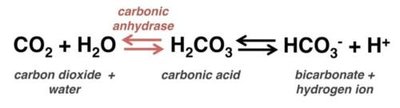

CO2 is transported in the blood as dissolved gas, carbaminohemoglobin, and bicarbonate. The following equation summarizes the conversion of CO2 to bicarbonate, which is crucial for acid-base balance:

Carbonic Anhydrase: Enzyme that catalyzes the reversible reaction between CO2 and water to form carbonic acid, which dissociates into bicarbonate and hydrogen ions.

pH Regulation: Removal of CO2 by the lungs helps maintain blood pH.

pH Regulation: By eliminating CO2, the respiratory system helps control blood pH.- CO2 is a biproduct of cellular respiration.